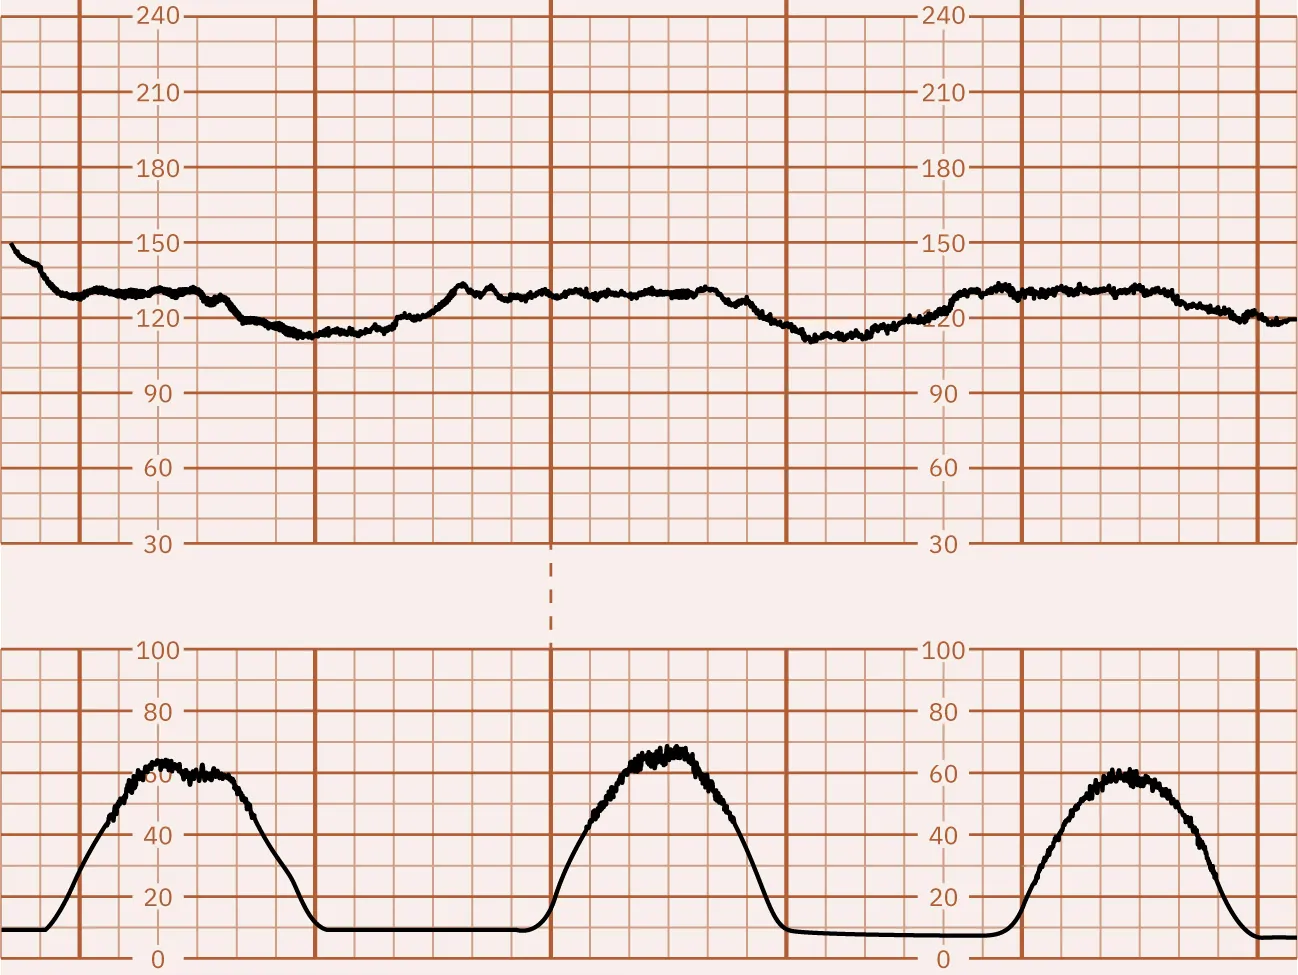

Explain how this monitor tracing shows adequate fetal oxygenation.

A screenshot of a fetal heart rate and contraction monitor with three separate graph panels. The top panel shows an orange line tracking fetal heart rate over time, with readings oscillating above and below 120 bpm against a dark background. The middle panel has a purple line displaying relatively flat uterine activity. The bottom panel depicts the intensity of contractions as white mountain-like peaks against a black background. Time stamps at the top right indicate the tracing spans from 23:54 to 00:12.